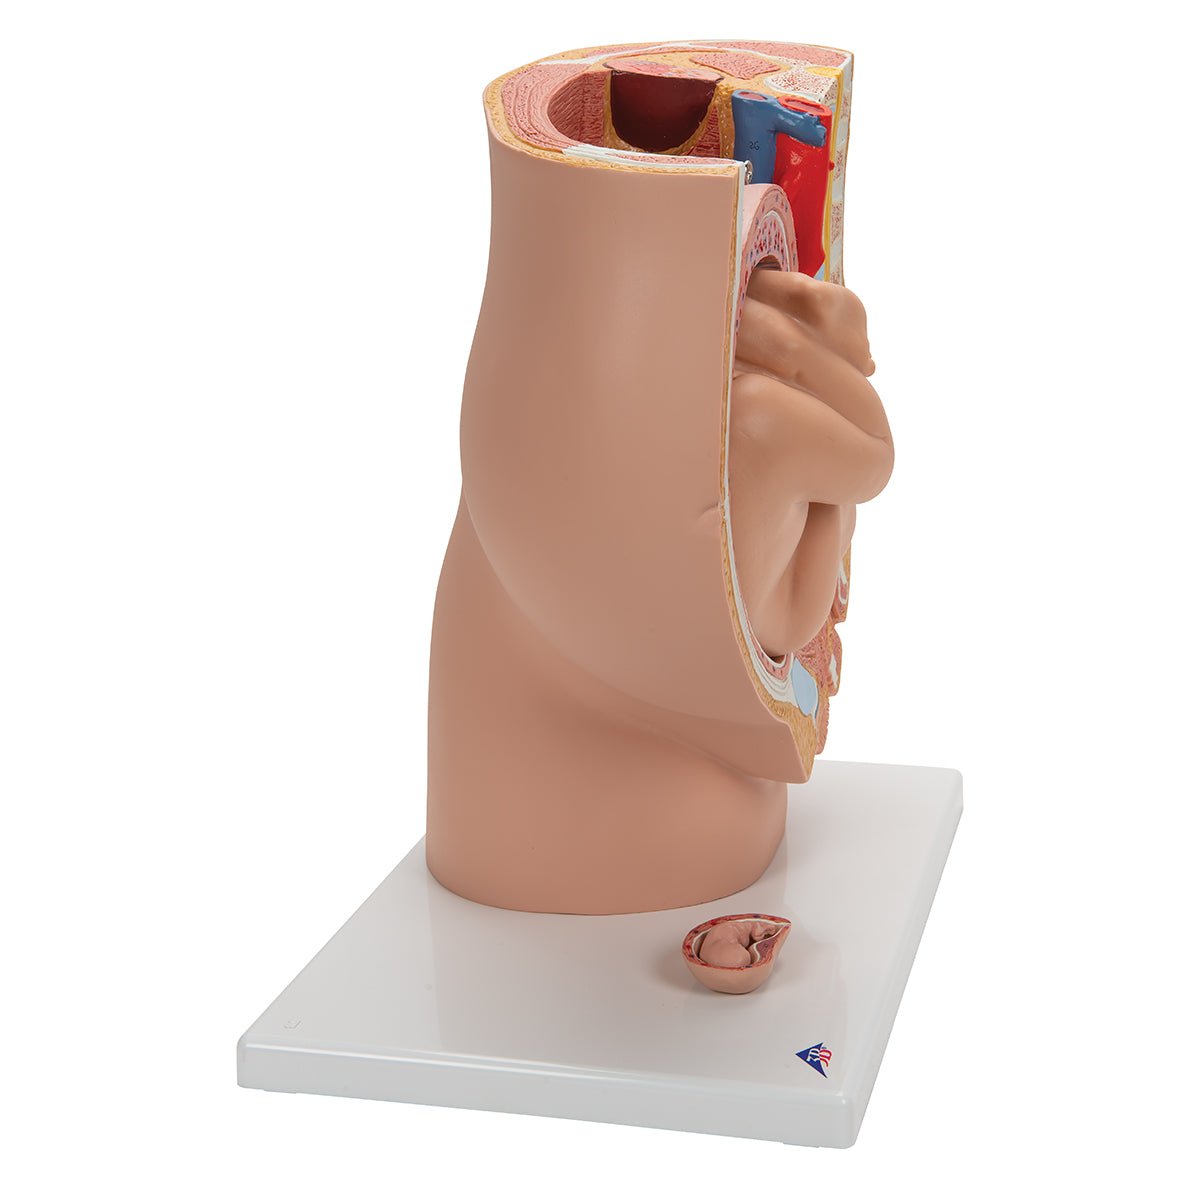

Selling anatomical models is the mainstay of eAnatomi, although we also spend a lot of resources developing our own anatomical materials such as posters. Anatomical models are used for various purposes and can show both defined tissues, organs and organ systems. Are you looking for a simple model of bone tissue or perhaps an advanced torso model based on MRI technology, you can find it all at eanatomi.com.